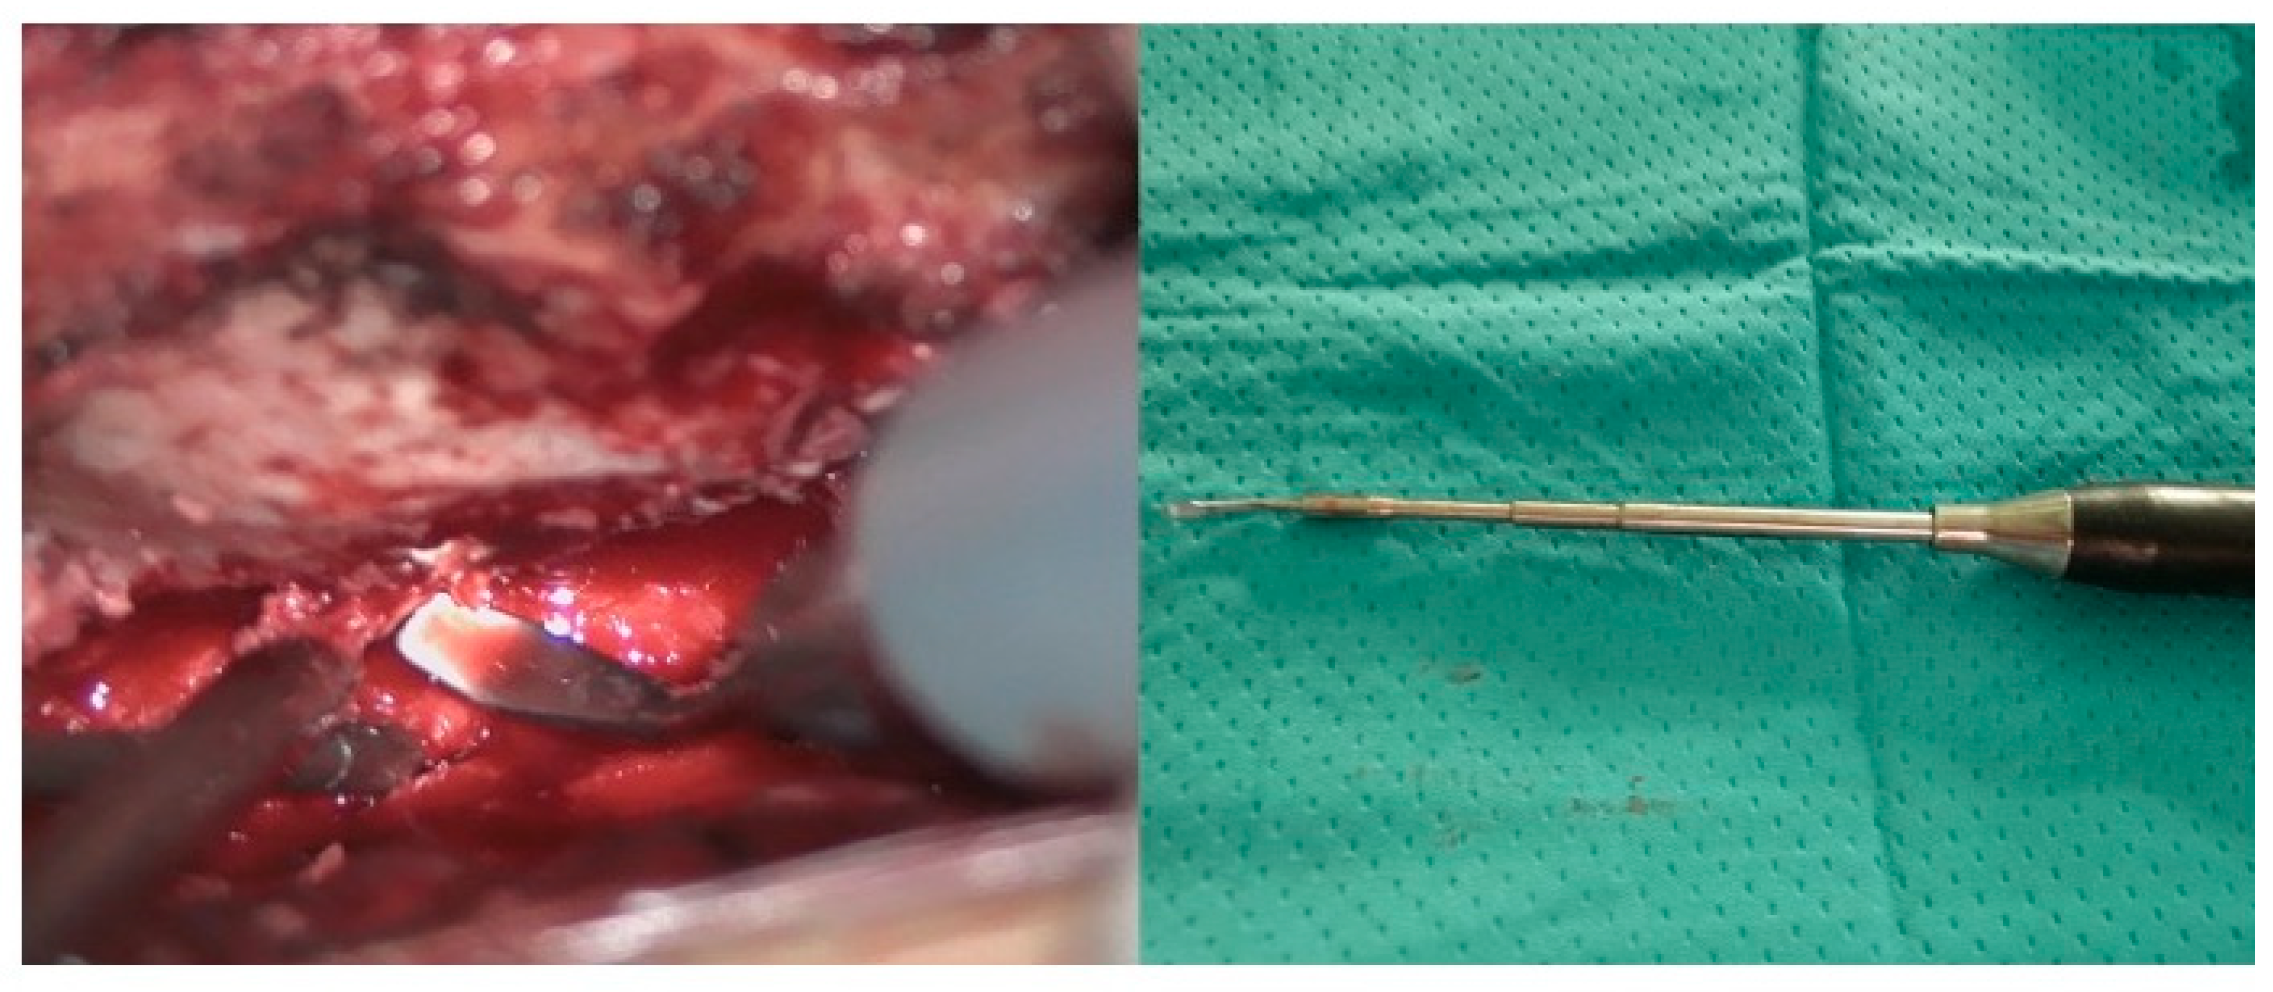

Figure 4.

Intraoperative findings. The hemangioma (red arrow) and arteriovenous fistula (yellow arrow).